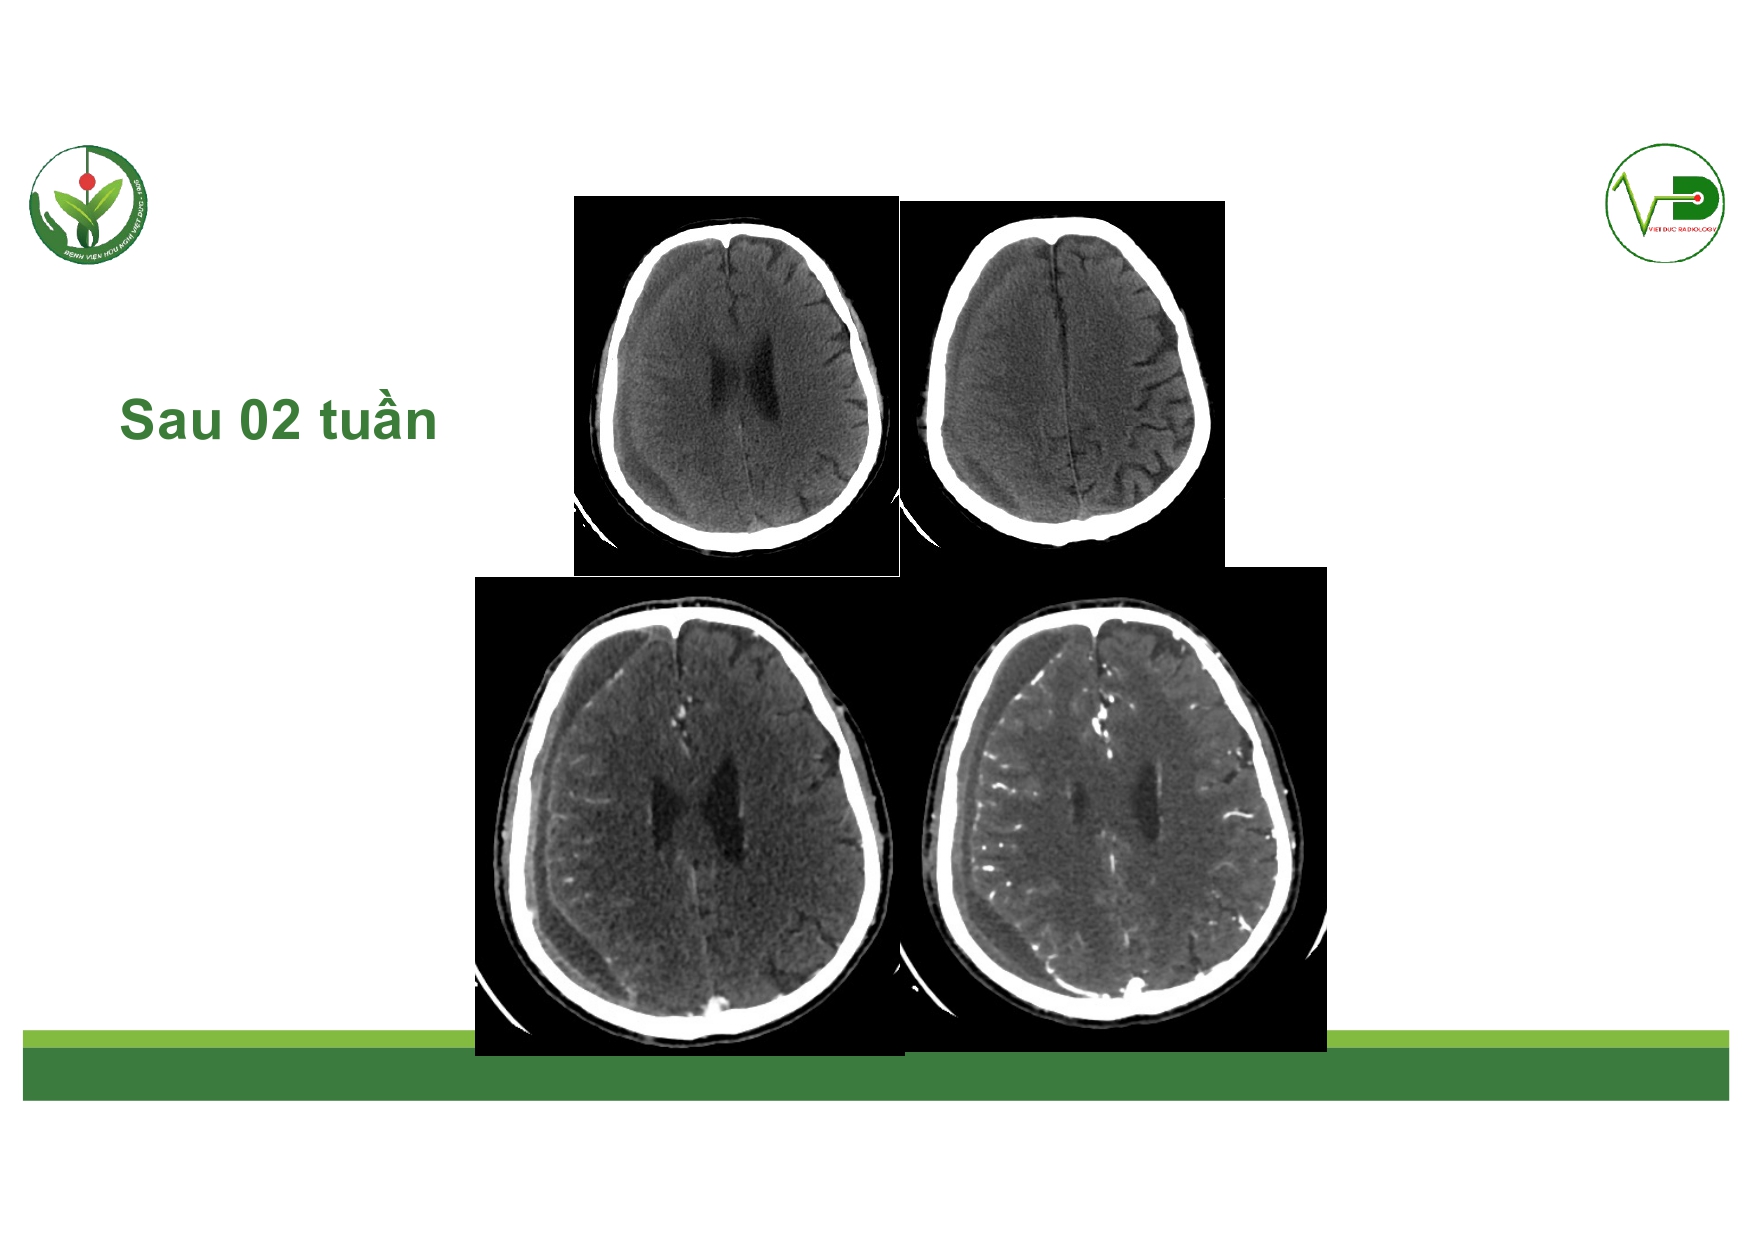

| 14:10 - 15:10 | DEBATE 2 | Recurrent chronic subdural hematoma– surgical or endovascular intervention? Surgical: Assoc. Prof. Duong Dai Ha Endovascular: Assoc. Prof. Le Thanh Dung | Moderator: Prof. Christian Matula Assoc. Prof. Duong Dai Ha | |

| 15:10 - 16:10 | Interactive Case Demonstration and Discussion II: ~20 minutes each, (5 minutes presentation followed by 15 minutes discussion) Practicals: How I am doing it? Participants present case presentations about how they do it? The faculty comment on and discussion. 1. Endoscopic approach in post-traumatic CSF leakage - Dr. Nguyen Thanh Xuan 2. Endovascular approach in CCF - Assoc. Prof. Le Thanh Dung | Prof. Christian Matula International & local faculties Participants | |